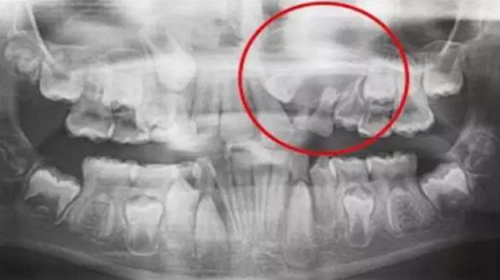

一名 23 區(qū)的9歲患者,在診所接受檢查時發(fā)現(xiàn)口內(nèi)中存在大范圍含牙囊腫[圖1]。由于上頜竇下沿出現(xiàn)大范圍突出,迫切需要接受囊腫去除手術(shù)[圖2和3]。

囊腫去除后的大量骨缺損[圖3]